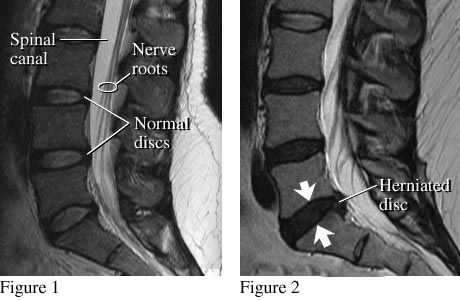

Images of normal discs and a herniated disc

Image courtesy of Intermountain Medical Imaging, Boise, Idaho. All rights reserved.

A side view of the lumbar spine shows normal discs, spinal canal, and nerve roots (see figure 1). Nerve roots normally float in the fluid-filled canal. Figure 2 shows a small herniated disc pushing into the canal toward nerve roots.